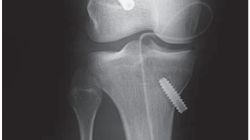

Witam. Rok temu miałem usuniętego kostniaka kostnawego z lewego podudzia. Będąc na konsultacji ortopedycznej w tym roku lekarz zlecił mi tomograf bo podobno RTG jest mało dokładne. Po zrobieniu tomografu lekarz na wizycie sprawiał wrażenie że ma problem z odczytaniem wyniku. Zapytał mnie czy boli mnie ta noga, odpowiedziałem że nie. Lekarz powiedział że wszystko jest w porządku ale jakoś tak bez przekonania i zlecił mi RTG które jest mniej dokładne od tomografu. Mam wykonać RTG i iść na wizytę za 3 tygodnie. Chciałbym zapytać czy jest tutaj jakiś lekarz który może zinterpretować mój wynik TK? " Stan po usunięciu kostniaka kostnawego lewej kości piszczelowej z widocznym ubytkiem warstwy korowej o wymiarach około 27x8mm. Jama szpikowa nierówna tkanka w jamie szpikowej o znacznie wyższej densyjności niż typowa tkanka szpiku kostnego co może odpowiadać zmianom bliznowatym. W sąsiedztwie ubytku pogrubiała warstwa zbita trzonu kości piszczelowej do 9mm przy 5mm grubości warstwy zbitej powyżej i poniżej ubytku." Z góry dziękuję za odpowiedź. Pozdrawiam